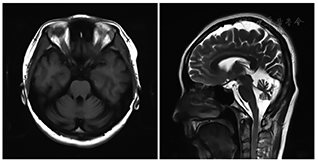

头颅核磁共振示小脑萎缩,皮层欠饱满(图1)。乳腺钼靶及超声检查发现右乳实性结节,乳腺影像报告和数据系统(BIRADS) 4类。考虑恶性病变不除外,完善PET-CT示:右乳外上象限1.4 cm结节影,放射性摄取略高,最大标准摄取值(SUVmax)为1.4;双侧小脑半球缩小,放射性摄取明显对称性减低。